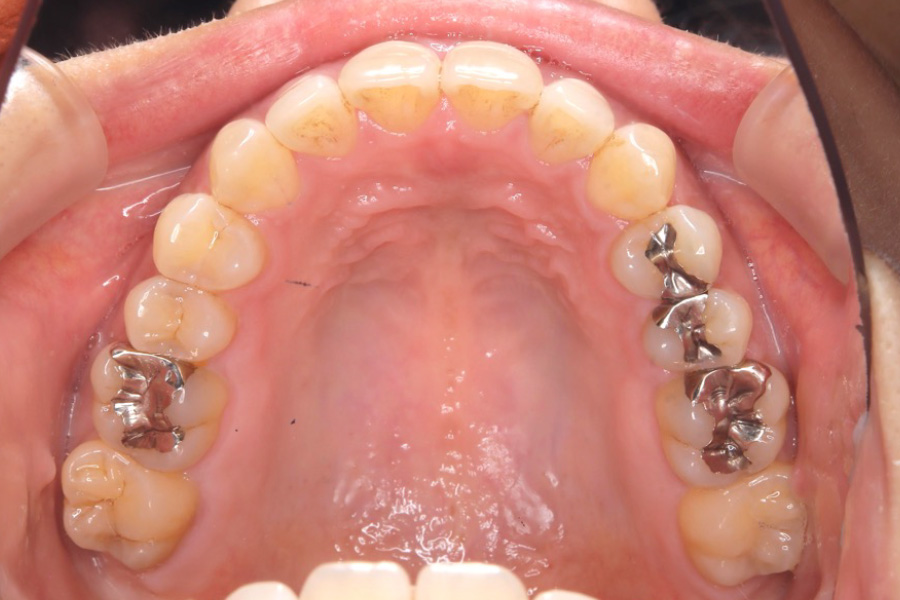

治療後